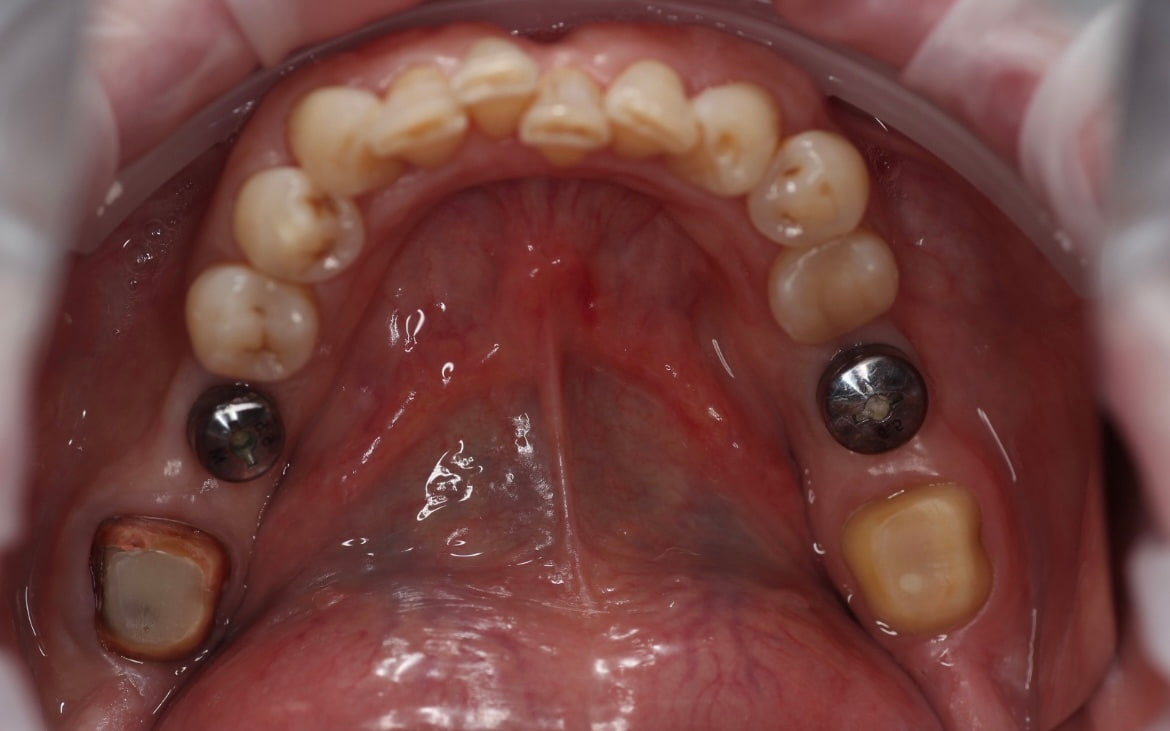

После проведений манипуляций по устранению рецессий и стабилизации десны в области 21 и 23, приступили непосредственно к протезированию: сняты первичные диагностические оттиски для моделирования будущих конструкций.

Обточка зубов 12-23 под дц коронки, ретракция 000 и 00 нитями, снятие рабочих оттисков а-силиконом, изготовление временных акриловых коронок прямым методом через силиконовый ключ, фиксация на TempBond.